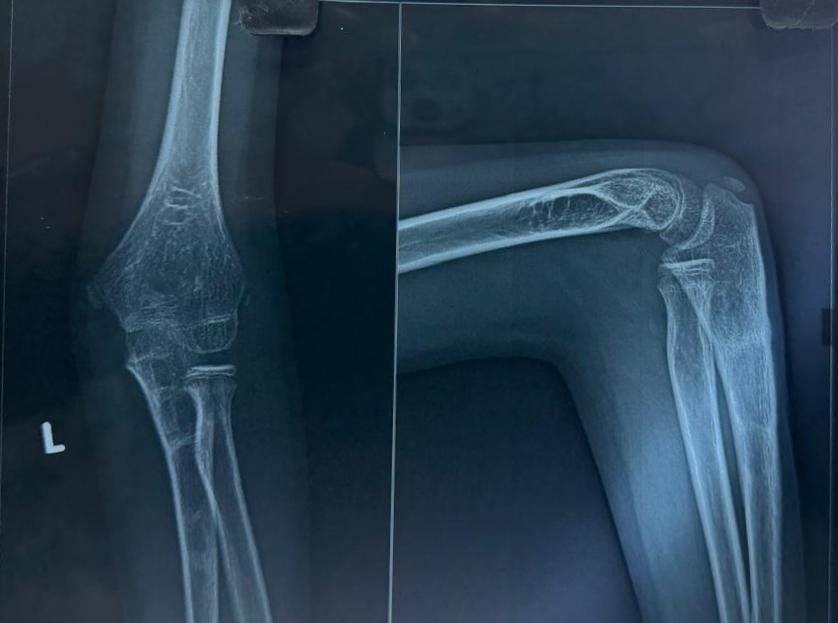

The post-operative course was uneventful. The limb was immobilized in an above-elbow slab for 3 weeks, followed by initiation of a gentle range of motion exercises under physiotherapy guidance. The child was monitored at regular intervals – 2 weeks, 1 month, 3 months, 6 months, 9 months, and 15 months post-operatively (Fig. 4, 5, 6, 7).

Figure 4: 1-month follow-up X-ray.

Figure 5: 3-month follow-up.

Figure 6: 6-month follow-up.

Figure 7: 9-month follow-up.

At each visit, clinical and radiographic assessments were performed. Over time, the child regained the movement in the wrist and MCP joint extension and thumb extension.

By the 9-month follow-up, radiographs confirmed complete union of the osteotomized ulna, and the radial head remained in a reduced, anatomical position. To prevent any implant-related complications, implant removal was done at 9 months (Fig. 8).